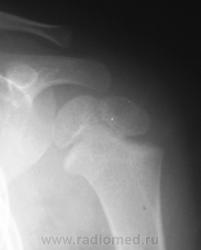

Для сравнения, дежурный хирург, попросил сделать правый плечевой сустав.

Перелом левой ключицы

Может быть, если есть клиника, но немного сомнительно. А почему опять нет второй проекции?